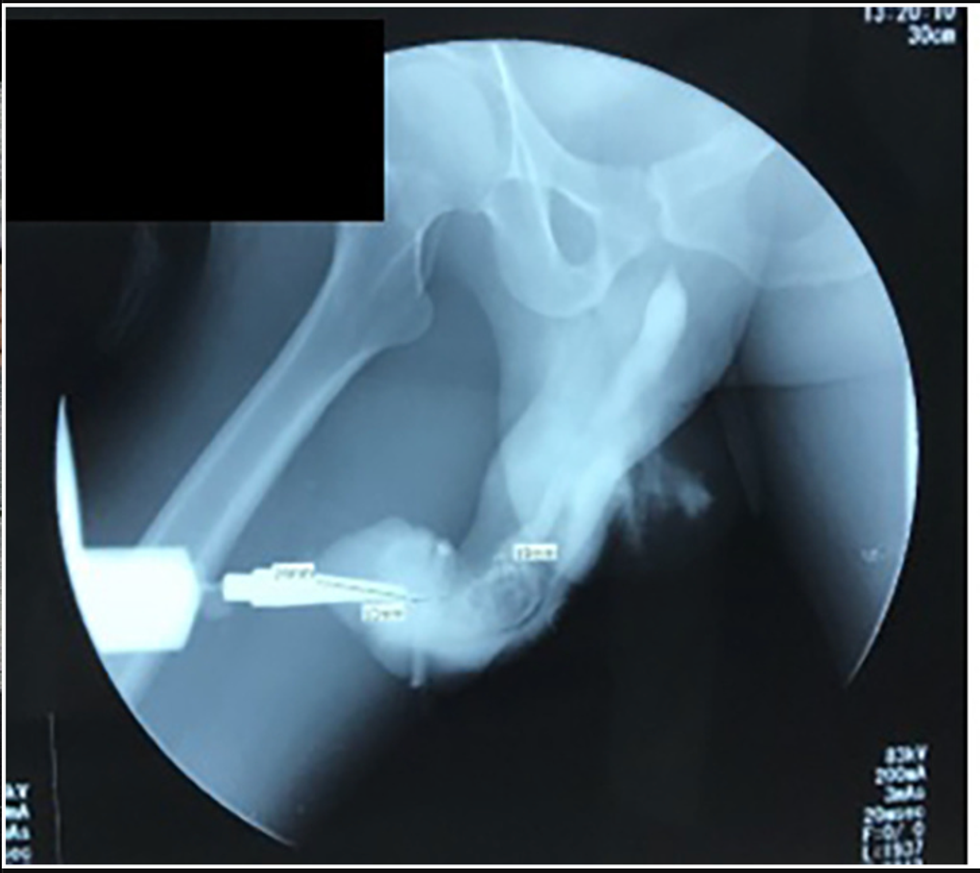

Upon examination, it was revealed that his member had turned purple due to the swelling and that the penis had skewered towards the right, as if to create a question mark-like shape.

The study notes that during intercourse the man felt a "crack" causing him to lose his erection and cause urethral bleeding. He also lost the ability to ejaculate.

If that wasn't enough, doctors also discovered a hematoma, otherwise known as a blood clot, that ran all the way from the tip of his penis to his scrotum. He also had a ruptured urethra which is likely to have impeded the urine flow.

To save the poor fellow's penis the doctors had to operate by first cutting open the penis and fixing the damaged urethra and penis tissue. The blood clot was then drained and he was fitted with an 'artificial erection' for an erectile exam.

Luckily for him, he passed the test and did have any further problems like fluid leakage or a continued bend in his penis. He was discharged after five days in hospital but had to urinate through a catheter for 21 more days.